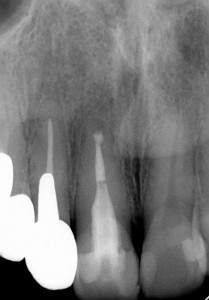

手術前 手術後 手術後1年

確かにしっかり治ってくれています。患者さんも喜んでくれています。